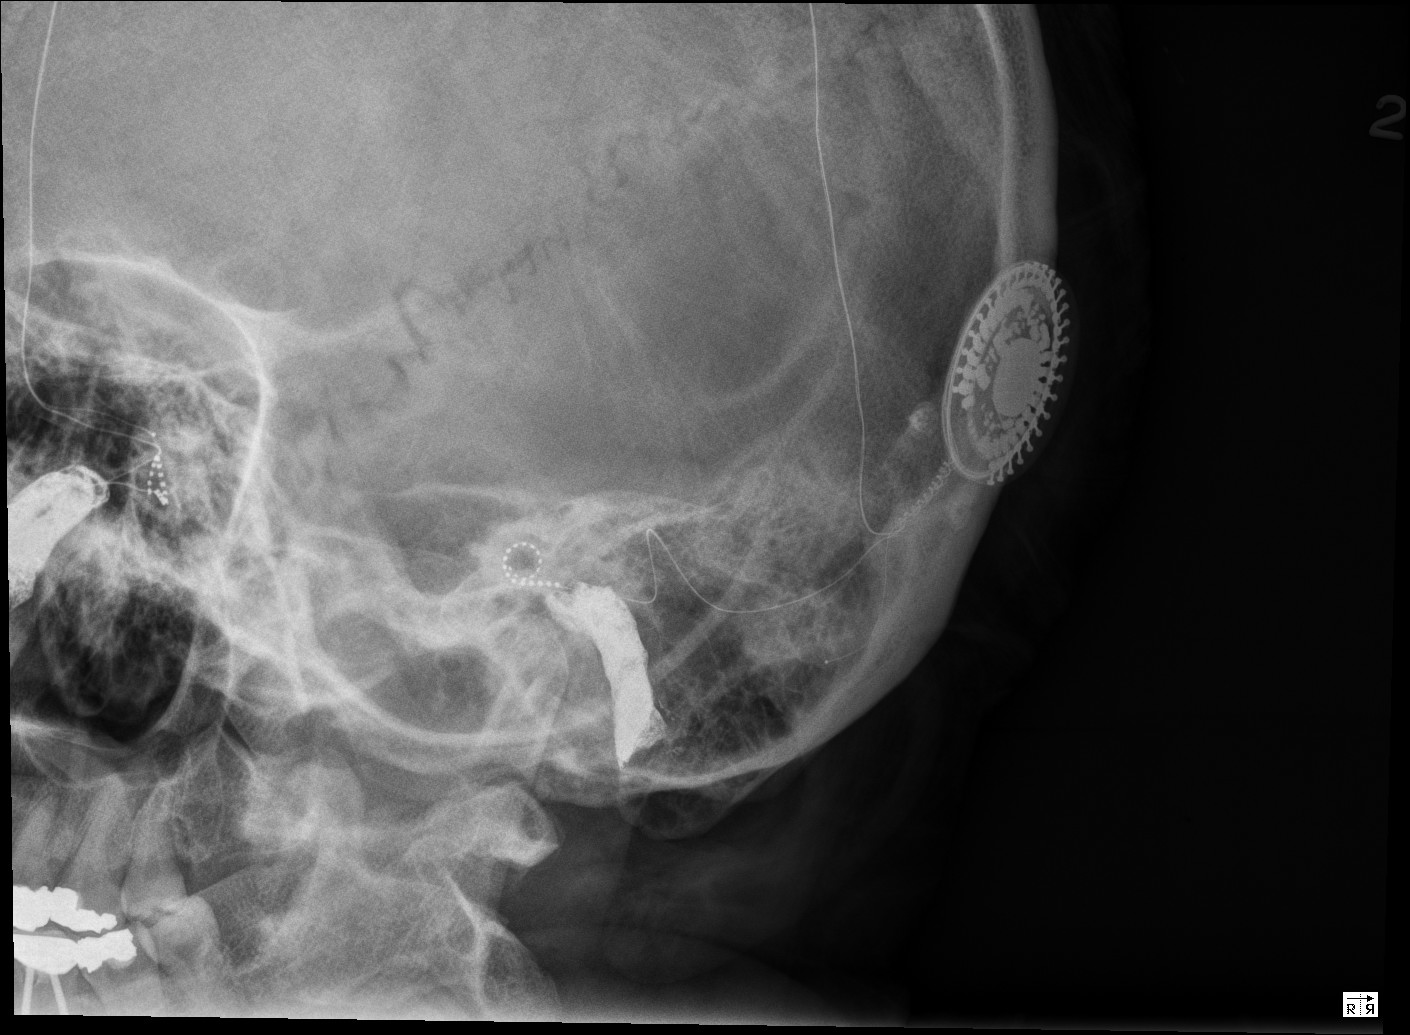

From www.researchgate.net

Modified Stenver's view of right cochlear implant with electrode tip Dental X-Rays And Cochlear Implants fortunately, she has been successfully treated with bilateral cochlear implants and speech processors. It can be a choice for people who have severe hearing loss from inner. a cochlear implant is an electronic device that improves hearing. the dental patient with a cochlear implant knows that there are surprises with noises that people with normal. As these. Dental X-Rays And Cochlear Implants.

Case 1. Plain Xray (reverse Stenver view) showing cochlear implant Dental X-Rays And Cochlear Implants fortunately, she has been successfully treated with bilateral cochlear implants and speech processors. the dental patient with a cochlear implant knows that there are surprises with noises that people with normal. It can be a choice for people who have severe hearing loss from inner. As these implants include metal elements, the. Likewise, ct scans , which provide. Dental X-Rays And Cochlear Implants.